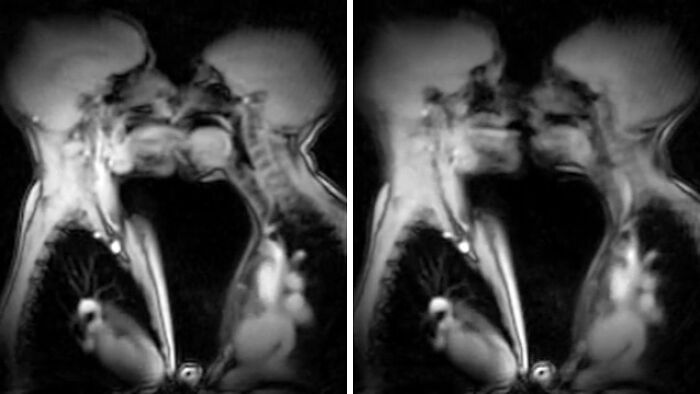

#72 This Is What Kissing In An Mri Scan Looks Like